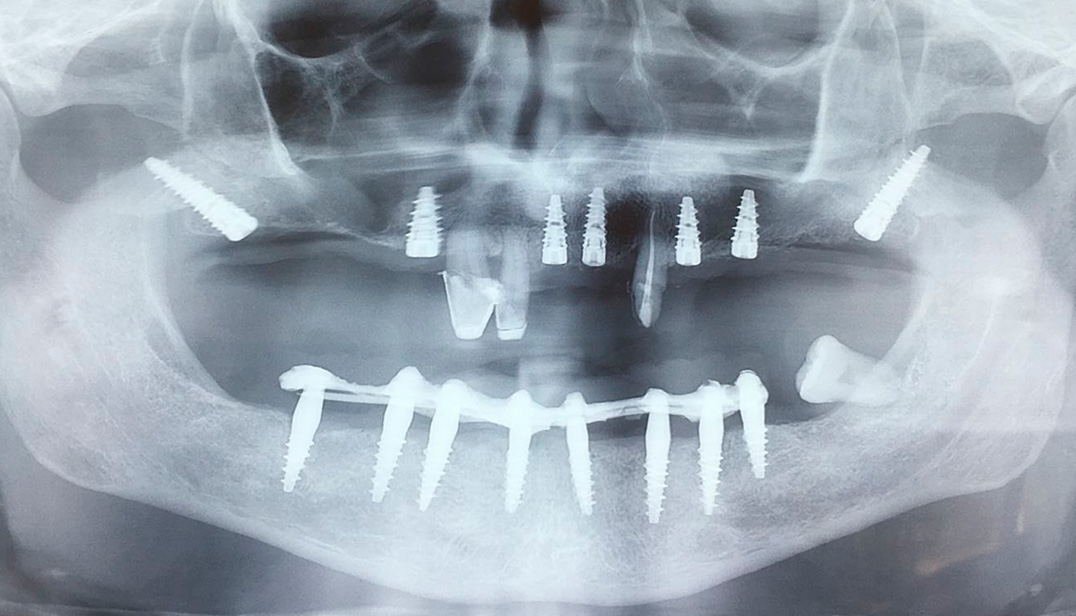

The pterygoid implants

In almost all cases of partial or complete edentation, partially removable or fully removable dentures are no longer accepted by patients. Even with serious bone loss, which makes it impossible or too risky to insert dental implants into the alveolar bone, today there are a number of reliable alternatives that allow not only to rehabilitate the entire arch from previously incurable conditions, but, above all, to do it quickly and without more invasive grafts or bone augmentation.

The dental implant is placed in the posterior part of the jaw in the usual way when the bone under the maxillary sinus is at least 6 mm. Until now, for large bone loss, it was necessary to resort to transplantation methods or sinus lift, or both, which were very invasive for the patient. Currently, implants are used that are supported by areas of bone farther from the alveolar ridge, for example, the pterygo-mandibular area.

The pterygoid implant is a dental implant that is installed behind in the upper dental arch, has an average length of 18 mm, which, starting from the maxillary tubercle, intersects the bony plates of the pterygoid fossa. The operation is performed under local anesthesia and lasts an average of about 20 minutes.

For a long time in dentistry, it was believed that the pterygo-mandibular area was not suitable for placing dental implants due to its anatomical characteristics. In more recent times, numerous clinical data have shown that this area is suitable not only for osseointegration of titanium dental implants, but also contrary to what was believed, the bone density of some pterigo-maxillary (wing-maxillary) structures ensures the stability of implant fixation even higher than that of any other parts of the jaw.

In addition, if conditions meet the requirements, a fixed temporary prosthesis can be placed within 24 hours after placement of the implants (immediate loading) emerging from the alveolar bone. At the end of the osseointegration period, the temporary prosthesis is replaced with a final fixed ceramic prosthesis. In cases of complete edentulism, the rehabilitation of the entire superior arch is obviously carried out by combining tuberous-pterygoid implants with other types of implants distributed in other areas of the mouth to provide a fixed prosthesis with a large number of attachment points.